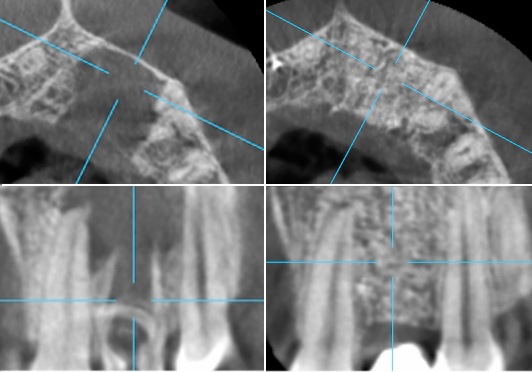

В данном случае показаны результаты удаления большой по размеру кисты челюсти. Важно, что жизнеспособность соседних зубов сохранена, при этом на месте кисты полностью восстановилась костная ткань.

До и после: Лечение кисты зуба

Большая киста в челюстии до операции

Большая киста через 1 год после операции